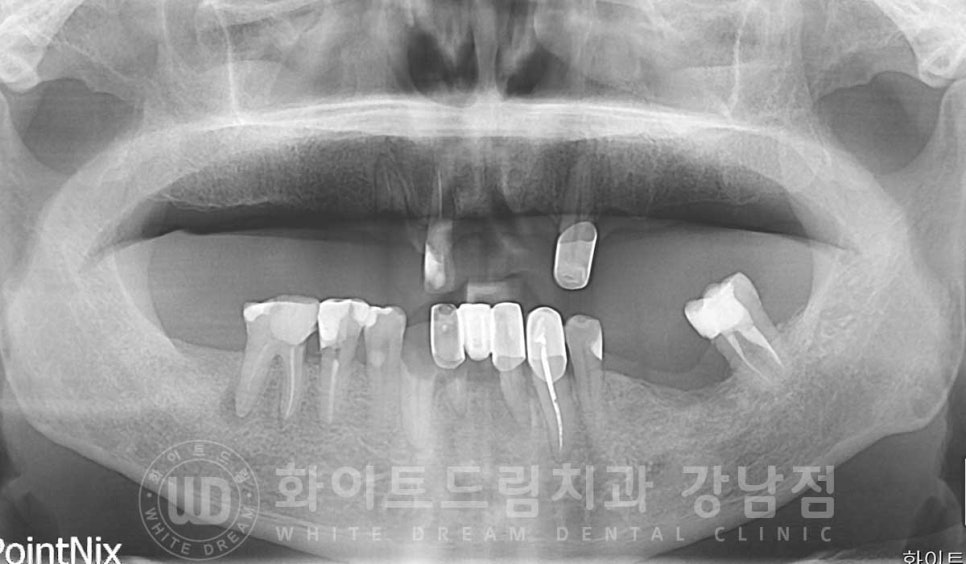

경기도 김포에서 내원을 해주신 70대 남성분이십니다.

치과 치료에 대한 공포감이 있으셔서 치료를 치일 피일 미루고만 계셨다가

저희 강남 화이트드림치과를 소개받아 내원해 주셨습니다.

초기 구내 사진을 보면 상악 치아들은 대부분 없으신 상태로

남아있는 보철과 치아의 상태가 좋지 못하신 분입니다.

환자분은 남아있는 치아들 중 23, 34, 44번 치아를 조금 더 사용하실 수 있으신 상태였으나

상악동의 경우 개인마다 모양, 위치, 크기가 각기 다른데

환자분의 경우 상악동의 위치가 높게 자리를 잡고 있는 상태입니다.

상악동이 높게 자리를 잡고 있으면

잇몸뼈의 길이가 임플란트를 식립하기에 적합하여 뼈이식 없이 수술이 가능한 경우들이 있습니다.

환자분의 경우 골 길이는 안정적이나

잇몸 염증으로 상악의 골폭 소실이 진행된 상태였습니다.

▲ 상악, 골폭이 모자란 부위

잇몸뼈의 길이가 임플란트를 식립할 수 있을 정도로 남아있지만

골폭이 모자란 경우는 임플란트를 감쌀 만큼의 충분한 잇몸뼈의 두께가 모자라다는 것으로

식립 후 나사선이 겉으로 잇몸뼈 밖으로 노출되기에

뼈이식, gbr(guided bone regeneration)을 동반하게 됩니다.

환자분은 골 소실이 심했던 부위, 23번 임플란트 부위는

뼈이식을 동반한 임플란트 치료를

동반하여 수술을 진행했고,

이 23번 임플란트는 보다 안정적이게 골 유착이 될 수 있도록

잇몸뼈 안에 매복을 해둔 상태로 수술을 완료하게 되었습니다.